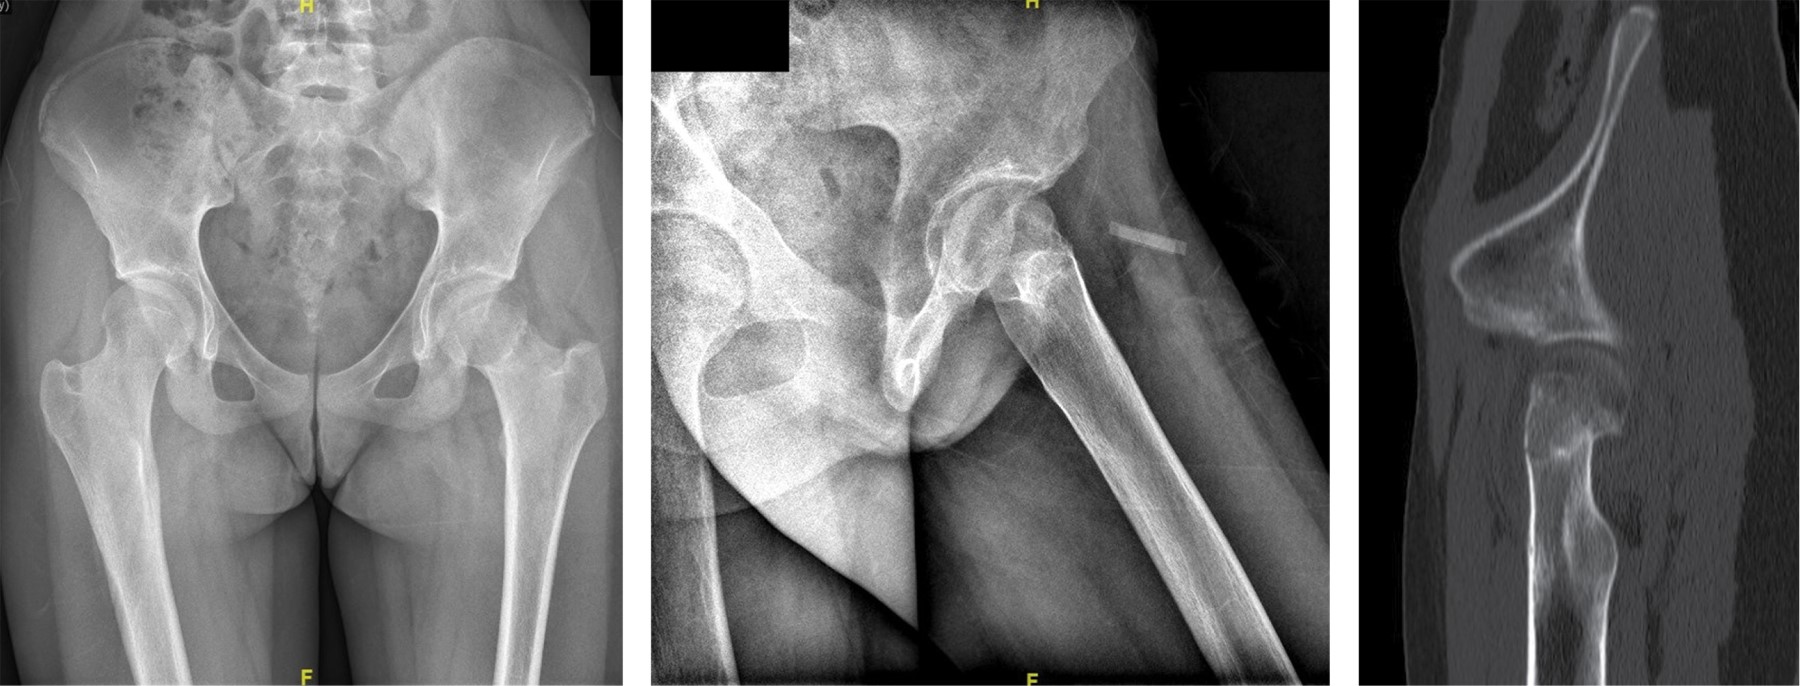

Figure 1